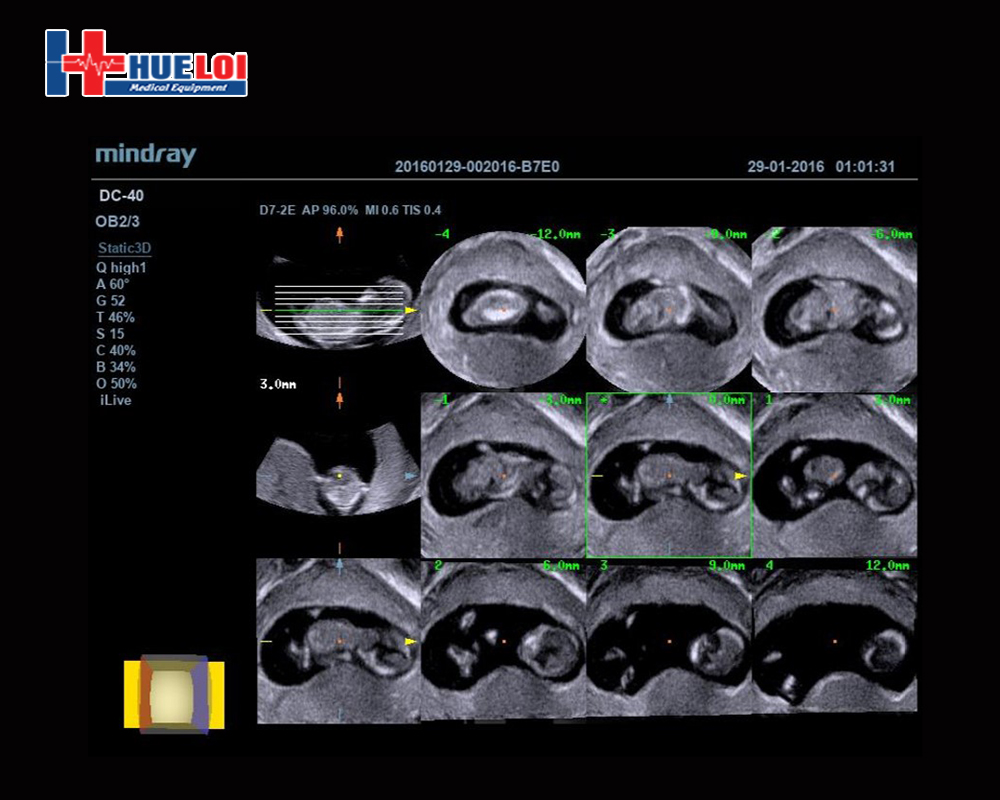

Hiển thị dữ liệu khối với nhiều mặt cắt 2D song song, giúp dễ dàng giải thích các cấu trúc giải phẫu, dành cho những trường hợp thăm khám khó cắt ảnh và giúp chẩn đoán tự tin hơn.